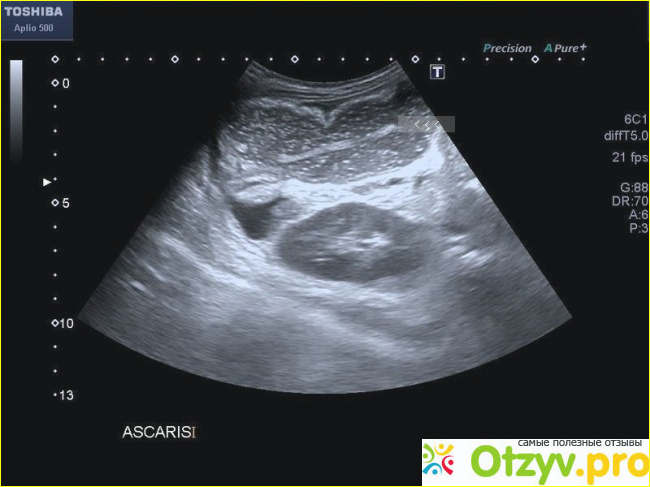

Пациенты этим интересуются очень давно и основательно. Насколько вредно проведение данной процедуры детям? Какую опасность представляет частой проведение УЗИ и не появятся ли после ее проведения какие либо серьезные проблемы со здоровьем? Многие считают, что этот метод исследования совершенно безопасен и можно особо не беспокоиться, другие же считают что это вредно или просто настороженно относятся к процедуре. Отрицательное отношение к данной процедуре привело к тому, что ее во многих странах просто запретили делать в ранние сроки беременности. Насколько это правильно – сказать сложно, ведь именно узи позволяет увидеть многие патологические состояния в ранних стадиях беременности, в частности – если ребенок расположился вне матки (так называемая внематочная беременность), многоплодная беременность (ее очень важно определить именно на ранних стадиях), какие либо аномальные формы беременности, когда отдельные органи или плод в целом формируется неправильно, особенно если есть предрасположенность к наследственным заболеваниям и порой такое было в прошлом у родителей. Если все эти патологии будут рано определены, то можно принять все меры, чтобы их устранить. Также следует не забывать, что метод ультразвукового исследования очень точен, чем не могут похвастаться многие методики и его сложно недооценить.